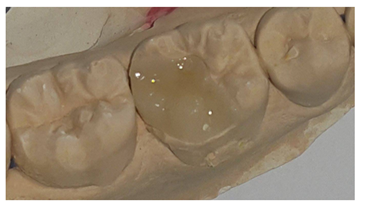

Then working cast was performed , and scanned, the onlay was designed referring to the corresponding shade matching , milled by CAD/CAM (Figure 5), and checked Intraorally.5

Figure 5 ceramic inlay/onlay by the system E max CAD.